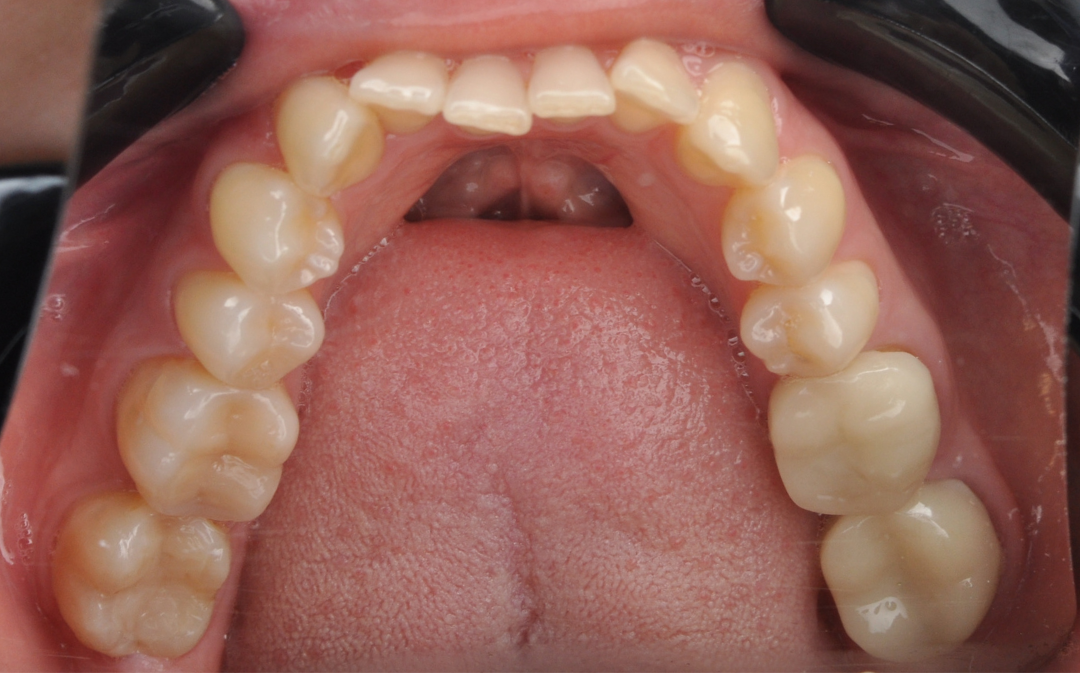

Этап №3

Ортодонтическая коррекция.

Стоматолог-ортодонт зафиксировал комбинированную брекет-систему (сверху керамические, а снизу – металлические брекеты).

Ключевые задачи ортодонта:

- Исправление прямого прикуса (одной из частых причин дисфункции ВНЧС).

- Изменение положения зубов.

- Доведение контактов челюстей до физиологически правильного смыкания.